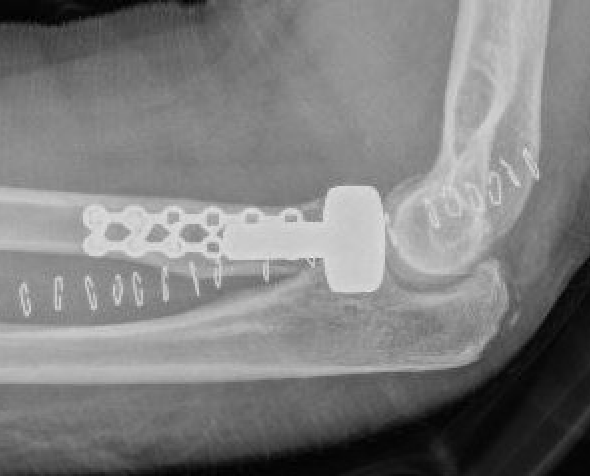

ORIF with plates

Technique

Lateral approach

- identify safe zone (90 degrees between radial styloid) and Lister's tubercle)

- lag articular surface first if required

- pre-contoured low profile plates

- distal limit is bicipital tuberosity

- check ROM intra-operatively

- plates often bulky and may limit ROM

- close annular ligament